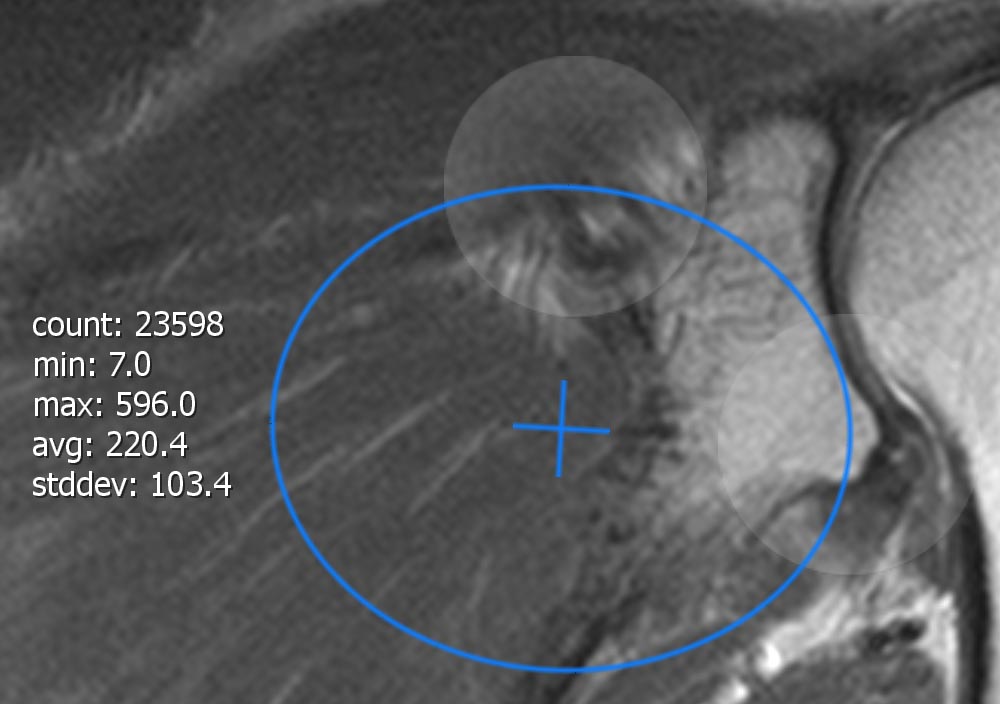

With the 'Region of interest' feature in the Toolmenu you are able to add a region of interest (ROI) to an image or a slice. After adding a ROI it is activated by default and ready for individualization. The ROI can be moved by tapping the cross in the middle of it and dragging it around. By using the two touch handles (white, transparent circles at the edge of the ROI) you are able to shape and rotate the ROI. On the opposite of the touch handles you’ll find the following information:

-

area: area (optional if image spacing is correct).

-

count: Number of pixels inside the ROI.

-

min: Smallest selected greyscale value.

-

max: Biggest selected grayscalwe value.

-

avg: Average grayscale value of all selected pixels.

-

stddev: Average spread of all grayscale values from the average grayscale value.

-

Attention

The same restrictions as for Segmentation apply.